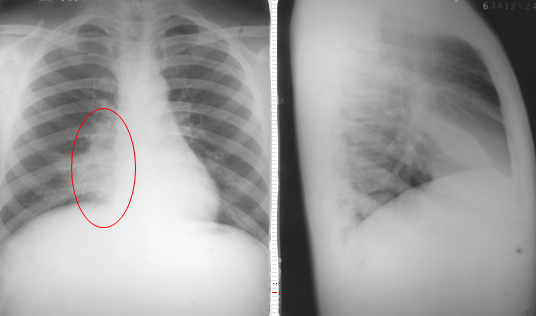

右肺中叶大叶性肺炎正侧位

图片

胸部正侧位片:右肺中叶见片状致密影,边缘模糊,局部呈剪影样改变(红圈所示)